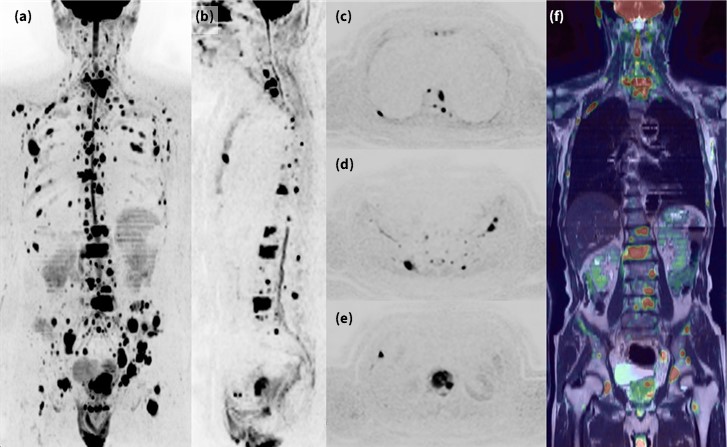

4. 最新技術を駆使した全身拡散強調画像(DWIBS)

DWIは他シーケンスと比べ低SNRかつ低分解能であることから、ARDLの恩恵を最大限受けるシーケンスと言える。SIGNA™ Voyagerは1.で述べたように、安定した広範囲撮像や脂肪抑制を有するためDWIBS検査を得手とするが、加えてARDLを活用することで高SNRかつ高尖鋭度への画質改善が図られ、検査の質向上に繋がると考える。また、Deep Learning 技術のみならず、AIR™ Reconによる受信チャンネル毎の重みづけや、受信感度の高いAIR AAコイルの使用により更なるSNR増加が期待でき、病変検出能の向上が期待できる。他方で、本装置で使用するAIR AAコイルは軽量素材であるため、比較的検査時間の長いDWIBS検査においては、被検者の負担を大幅に軽減できる点も特筆すべき事項である。

Fig.4に前立腺がんの多発骨転移の症例を示す。ARDL等の技術を駆使することで、従来条件より尖鋭性の高い画像が可能となり、また高い病変検出能を有していることがわかる。さらに、MIP画像の病変視認性のみでなく、Axial元画像のクオリティも高く、安定した画像が取得できていると言える。またフュージョン画像では、画像の位置一致率が高く、歪みの影響が最大限抑制されていることがわかる。

DWIBSはSNRの観点より、近年3T装置での検査報告が散見されるが5)、ARDLがDWIに適用されたことで、画像歪みや脂肪抑制の安定性からも1.5T装置での有用性が高く、SIGNA™ VoyagerでのDWIBS検査はより安定した高画質が取得可能であると言える。

Fig.4 前立腺がん多発骨転移におけるDWIBS画像(axial 4stationにて撮像)

(a)MIP (b) partial MIP sag (c)(d)(e) axial(元画像) (f) Fusion image(SSFSE+DWI)